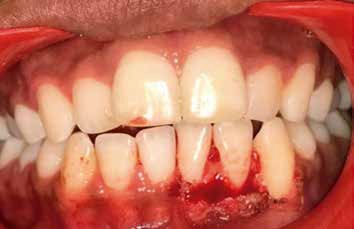

A 24-year old female reported to the department of Oral Medicine & Radiology, with a chief complaint of painless growth on gums in lower left front teeth region since last 2 years. History revealed that the growth was initially small in size but from past 7 months, it gradually increased to attain present size. There was history of occasional bleeding during mastication, tooth brushing and spitting, leading to salty taste in the mouth. There was no history of past trauma, chronic irritation, recent weight loss, systemic rise in temperature, parasthesia/numbness and similar growth elsewhere in the body. The Past dental/medical history was non contributory.The general physical examination revealed that all the vital signs were within normal limits. No gross facial asymmetry was appreciated on extra oral examination. (Figure 1a) The intraoral examination revealed a well circumscribed, solitary, oval shaped, erythematous & pedunculated growth present on labial gingiva involving interdental papilla between 31, 32, 33. The growth extended antero-posteriorly from mesial aspect of 31 to distal surface of 33 and superiorly up to middle of coronal portion of 31, 32, 33 with approximate size of 1.5 x 2cm. The overlying mucosa of growth appeared rough, lobulated, pinkish in color with interspersed reddish areas. (Figure 1b) On palpation, the growth was firm to hard, non-tender. On probing, pseudo pockets were found irt 31, 32,

33. No discharge on palpation from growth was seen. Calculus was present between 31, 32, 33 teeth. On the basis of history & clinical examination, a provisional diagnosis gingival epulis was made. The differential diagnosis considered was traumatic firoma, pyogenic granuloma, Peripheral fibroma with calcification, Peripheral Cemento-ossifying fibroma, and Peripheral giant cell granuloma. The intraoral periapical radiograph 31, 32, 33, 41 and orthopantomographic (OPG) examination showed no obvious bony changes. (Figure 2 a & b). All the hematological reports were in normal limits. Later with patient consent, excision of the lesion was done under local anesthesia (Figure 3) and the specimen was sent for histopathological examination, which showed parakeratinzed stratified squamous epithelium of variable thickness with evidence of ulceration in some areas. The underlying dense fibrous connective tissue shows varying degrees of cellularity along with foci of mineralization. The hard tissue component showed basophillic acellular spherules. There was presence of focal chronic inflammatory cell infiltrate and granulation tissue formation in some areas. These features were suggestive of peripheral cemento-ossifying fibroma. (Figure 4) In the present case, after excision of the lesion, all the remnant of the lesion was removed and thorough debridement was done. Capsule amoxicillin (500mg), tablet metronidazole (400mg) and tablet ibuprofen (400mg) were prescribed to the patient thrice daily for five day postoperatively, to relieve the pain and to prevent secondary infection Following this, close monitoring was done after 10 days, 1 month, 3 months and 6 months and no recurrence was observed. The surgical site appeared to be healing well. The patient was asymptomatic, aesthetically sound and satisfied with results on follow up.